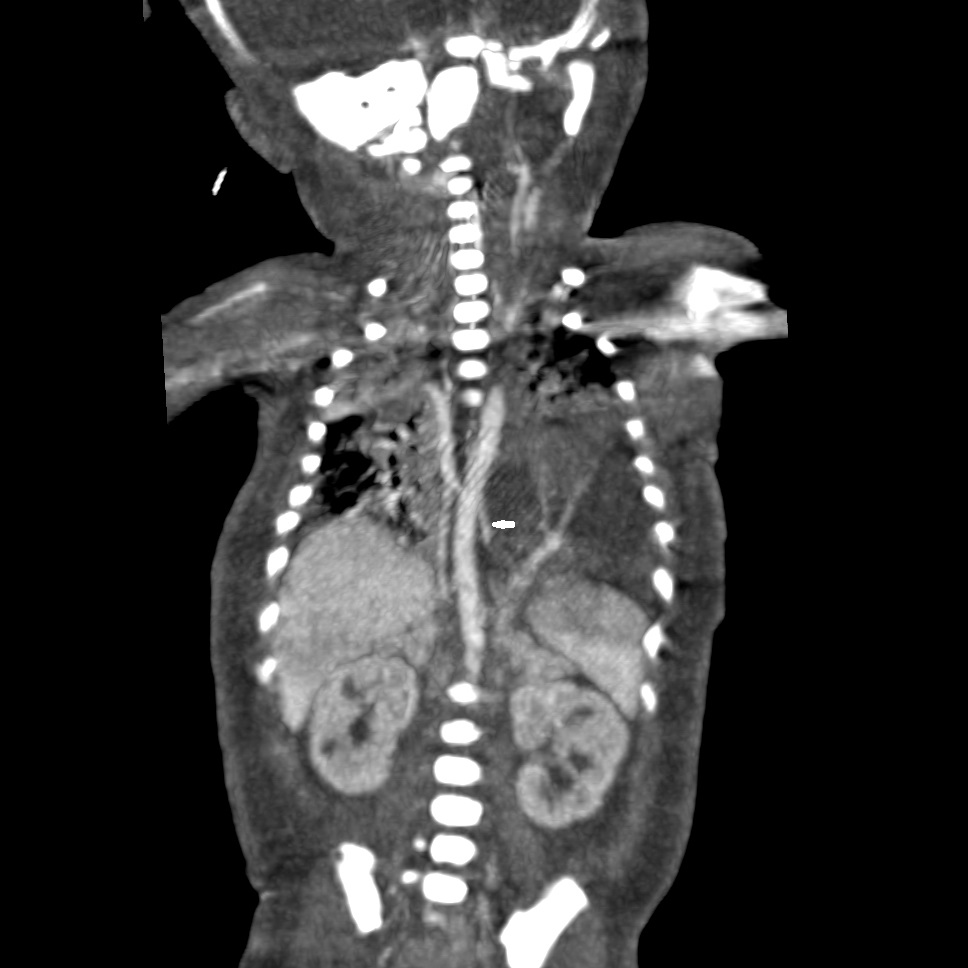

A 36-year-old lady, (G3P1L1A1) 27+6 weeks gestation, presented to our fetal medicine department with an ultrasound study showing a hyperechoic intrathoracic mass in the fetal left hemithorax measuring 3.8x3.1x3.5cms, which was separate from the fetal lung with a large vessel arising from the aorta perfusing it (Fig.1). There was gross left-sided pleural effusion with mediastinal shift causing pseudo-dextrocardia and ascites with hydrops. A diagnosis of BPS with severe NIH was made. There was significant blood flow across the tricuspid valve and descending thoracic aorta, which implied that the fetal hydrops was due to high-output cardiac failure secondary to a ‘diastolic run-off’ from the aorta.

Ultrasound image of BPS with severe NIH.